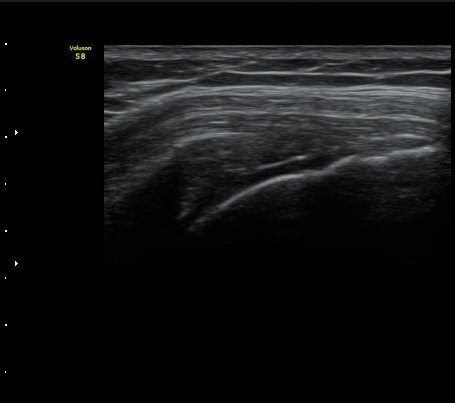

±Ø»ó°Ç Ⱦ´Ü¸é°Ë»ç»ó »ó¿Ï°ñµÎ¸¦ µ¤°í ÀÖ¾î¾ßÇÒ ±Ø»ó°ÇÀÌ º¸ÀÌÁö ¾Ê°í Á¡¾×³¶ÀÌ ÆíÆòÇϰÔ

³»·Á ¾É¾Æ º¸ÀδÙ(±×¸² 3).